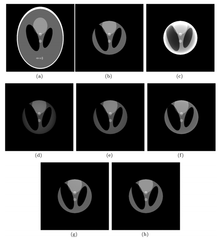

In iterative reconstruction in digital imaging, interior reconstruction (also known as limited field of view (LFV) reconstruction) is a technique to correct truncation artifacts caused by limiting image data to a small field of view. The reconstruction focuses on an area known as the region of interest (ROI). Although interior reconstruction can be applied to dental or cardiac CT images, the concept is not limited to CT. It is applied with one of several methods.

The first interior-reconstruction method listed below is extrapolation. It is a local tomography method which eliminates truncation artifacts but introduces another type of artifact: a bowl effect. An improvement is known as the adaptive extrapolation method, although the iterative extrapolation method below also improves reconstruction results. In some cases, the exact reconstruction can be found for the interior reconstruction. The local inverse method below modifies the local tomography method, and may improve the reconstruction result of the local tomography; the iterative reconstruction method can be applied to interior reconstruction. Among the above methods, extrapolation is often applied.